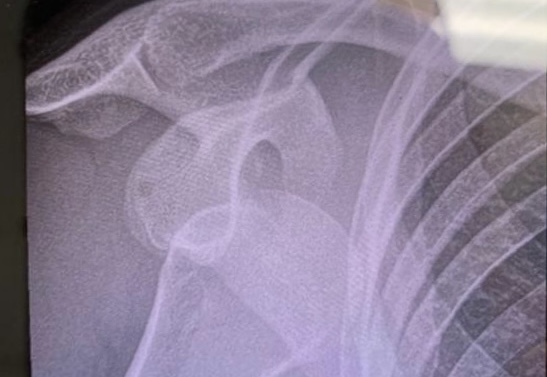

An Ode To (Not) Being Rachel Atherton

Hannah recently dislocated her shoulder. Like Rachel Atherton, she didn’t actually crash… but she wasn’t actually riding. Rachel’s shoulder popped…